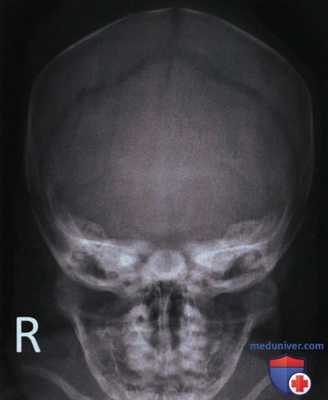

РИСУНОК 1 Рентгенограммы черепа в ЗП и ПЗ проекциях, правильное расположение. РИСУНОК 2 Рентгенограмма нижней челюсти в ЗП проекции, правильное расположение.

• Череп: расстояние между латеральным краем глазницы и латеральным краем черепа с обеих сторон одинаково (рис. 4)

РИСУНОК 3 Правильное положение пациента для рентгенографии черепа в ЗП проекции. РИСУНОК 4 Рентгенограмма черепа в ЗП проекции. Голова была повернута лицом влево. РИСУНОК 5 Рентгенограмма нижней челюсти в ЗП проекции. Голова была повернута лицом вправо. РИСУНОК 6 Рентгенограмма черепа в ЗП проекции. Подбородок был опущен недостаточно, чтобы расположить ОМЛ перпендикулярно ПИ. РИСУНОК 7 Рентгенограмма черепа в ЗП проекции. Подбородок был опущен избыточно, чтобы расположить ОМЛ перпендикулярно ПИ.

Если на рентгенограмме черепа в заднепередней (ЗП) или передне-задней (ПЗ) проекции расстояние между латеральным краем глазницы и латеральным краем черепа с одной стороны больше, чем с другой (рис. 4), то голова была повернута лицом в ту сторону, на которой указанное расстояние меньше.

ПЗ проекция черепа.

а) Анализ. Расстояние между латеральным краем глазницы и латеральным краем черепа справа больше, чем слева. Голова была повернута лицом влево. Каменистые гребни визуализируются ниже надглазничных краев; подбородок был опущен недостаточно, чтобы расположить ОМЛ перпендикулярно ПИ.

б) Коррекция. Поверните голову лицом вправо так, чтобы срединная сагиттальная плоскость располагалась перпендикулярно ПИ. Опустите подбородок так, чтобы ОМЛ была перпендикулярна ПИ, или наклоните ЦЛ в каудальном направлении.